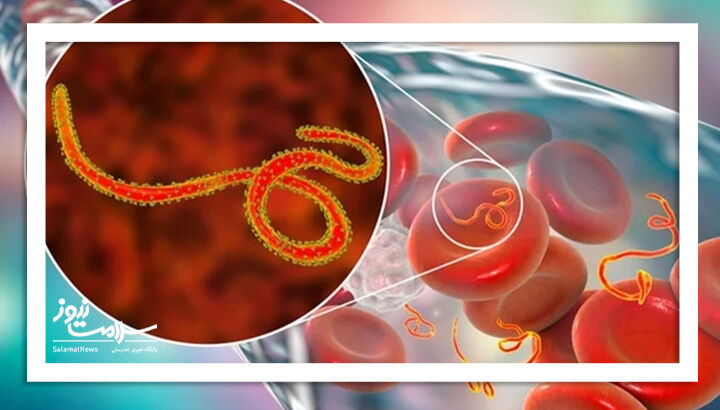

سازمان جهانی بهداشت هشدار داده است که شیوع ابولا در آفریقا میتواند «بسیار بزرگتر» از آنچه اکنون...